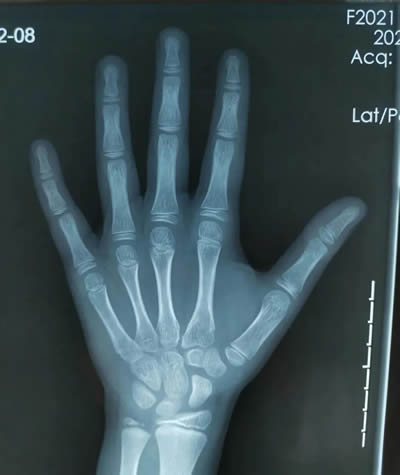

評估骨齡最常見的方法是拍攝左手(包含全掌和腕部)X光正位片。具有操(cāo)作簡便、檢查時(shí)間短、檢查費用低的特點,故目前仍以X線平片作為骨齡評估的主要手(shǒu)段(duàn)。臨床上評估骨(gǔ)齡以左手及腕關(guān)節作為(wéi)最常見的評(píng)測部(bù)位,通過觀察相應的(de)腕部骨化中心、左手掌指骨骨(gǔ)化中心的個數、形態來評估骨齡。因此,獲得用於骨齡評估的左手及腕關節的圖(tú)像是骨齡評估的第一步。骨齡圖像的關鍵骨化中心包括遠端橈骨、遠端尺骨、腕骨。

徐州市婦(fù)幼保健院為準確測算骨齡,由放射科(kē)專業人員攝片獲取標準X線片圖像,通過(guò)準確定位,清晰拍攝,保證手腕骨的影像質量。另外,醫院還(hái)引進了先進的骨齡影像智能檢測係統,該係統(tǒng)依(yī)據臨床常用指標(包括兒童身高體重,父母身(shēn)高等參數),可自動生成詳細完善的診(zhěn)斷報告,包含骨齡評價、身高評價、發育評(píng)價、身高預測(cè)等(děng)指標。隨後,結合專業骨齡讀片醫生人工讀片(piàn),既能(néng)夠保證結果的(de)精準度,同時(shí)也能夠提高讀片的效率。